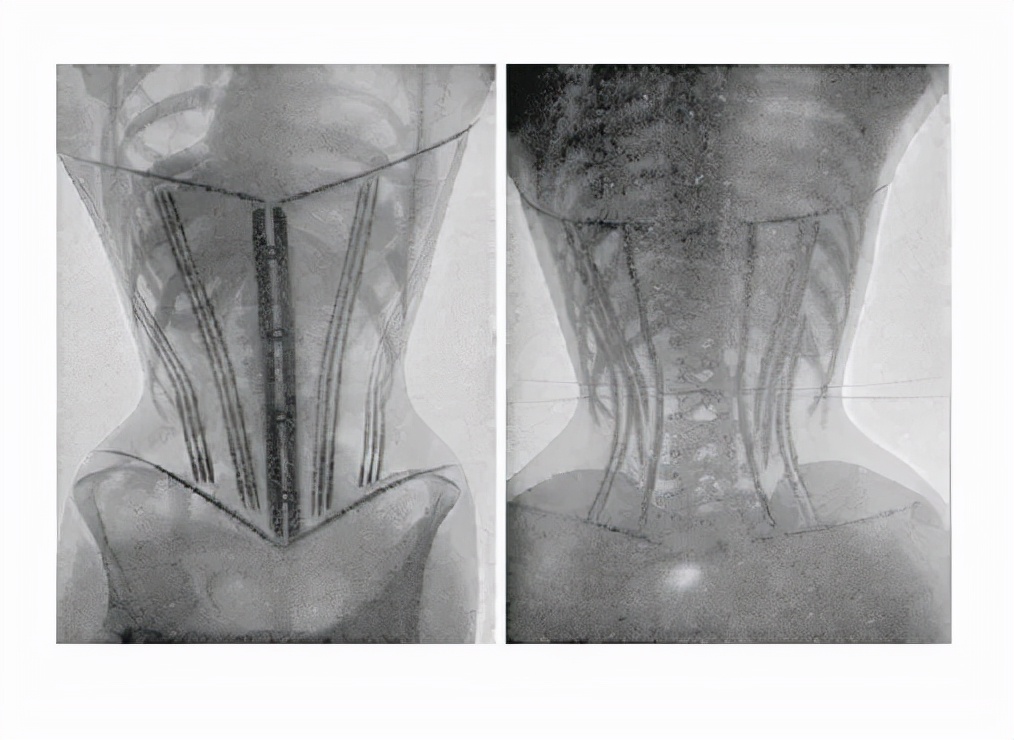

束缚带怎样用更科学?

收腹带种类很多,有纱布式的、松紧带式的、内裤式的、腰带式的,但基本原理都是一样的,加快恶露排尽。

如果是为了促进伤口愈合,比如剖腹产,产后3-4天就可以使用束缚带。建议使用10-14天。

如果戴束缚带想起到收腹效果,产后束缚带的使用必须在明确盆底肌完全恢复的情况下才可佩戴。

建议妈妈产后42天后回到医院做盆底肌评估筛查,如果盆底肌没有问题,才可以使用束缚带。

如果盆底肌存在问题,比如盆底肌松弛,就应先进行盆底肌康复治疗,等盆底肌恢复后才能戴束缚带。

使用束缚带的过程中不能全天都绑着,在床上躺着或者坐着休息时应适当解开,等到下床活动时再绑上。如果长时间使用束缚带,很可能会影响腹部血液循环,对腹肌和腰背肌的肌肉都很不利,导致产后恢复时间延长。

过紧的使用束缚带,肉眼看腰部变细啦,其实是增加了腹部的压力,加重盆腔脏器的脱垂。